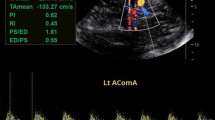

Does the TCD imaging (TCDI) technique obtain velocities similar to the non-imaging technique used in STOP?

If using TCDI, what velocity criteria should be used?

Correlation studies between TCDI systems and TCD have shown a systematic offset of about 10%, with TCDI measurements of systolic or time-average of the mean of the maximum (TAMMX) measured lower than TCD for the same patient. Accordingly, to be comparable to a 200 cm/s TAMMX using TCDI, the velocity cutoff of 185 cm/s has been recommended [20].

Can peak systolic be used instead of TAMM?

This question was recently examined using data from the STOP study by comparing stroke prediction between systolic and TAMMX velocities from the same examination [21]. This was possible because in STOP the reader read both the peak systolic velocity (PSV), the diastolic (DV) and the TAMMX in a blinded fashion, although only TAMMX was considered in the STOP trial itself. In this report, TAMMX and PSV were superior to DV, and PSV appeared to predict stroke as well as TAMMX. The authors recommended these cut points for PSV when using TCDI compared to TAMMX from TCD.

System used | Velocity | High risk (cm/s) | Conditional (cm/s) |

|---|---|---|---|

TCD | TAMMX | 200 | 170 |

TCDI | PSV | 250 | 200 |